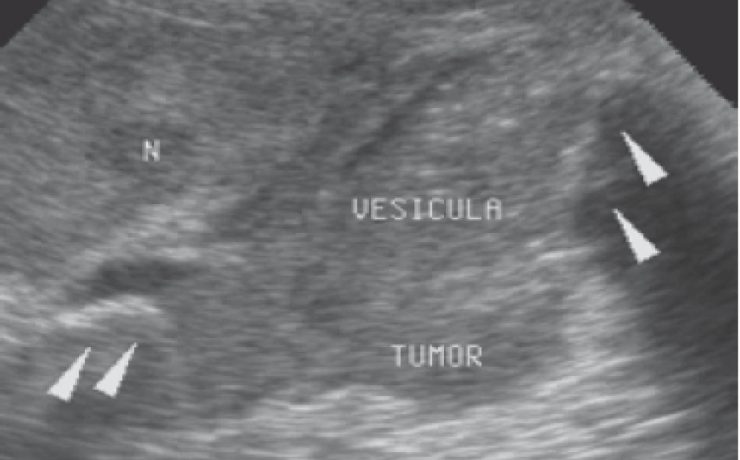

SEGMENTACIÓN HEPÁTICA. EVALUACIÓN ECOGRÁFICA

El hígado se encuentra en el hipocondrio derecho, pesa 1.5 a 2 kg en el adulto y se encuentra mantenido en su posición por la vena cava inferior, las venas suprahepaticas, el ligamento redondo del hígado y los ligamentos coronales y triangulares. Viendo al hígado de manera anterosuperior, se divide